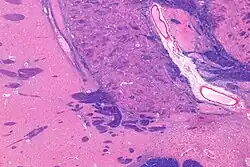

MRI showing a coronal plane of the head with marks showing the location of the substantia innominata, the region in which the nucleus basalis is found. | |